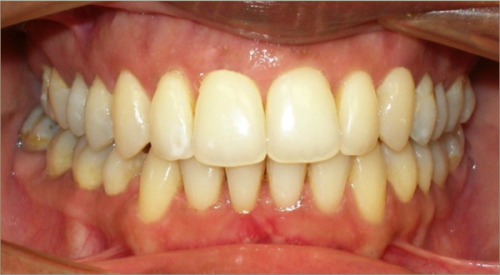

32 year old female:

Diagnosis:

- Previously lost upper first molars

- Severe lower arch crowding

- Midline discrepancy

- Narrow upper arch form

Treatment:

- Extraction of lower right first bicuspid

- Substitution of upper second molars for first molars

- Full fixed appliances

- 23 months